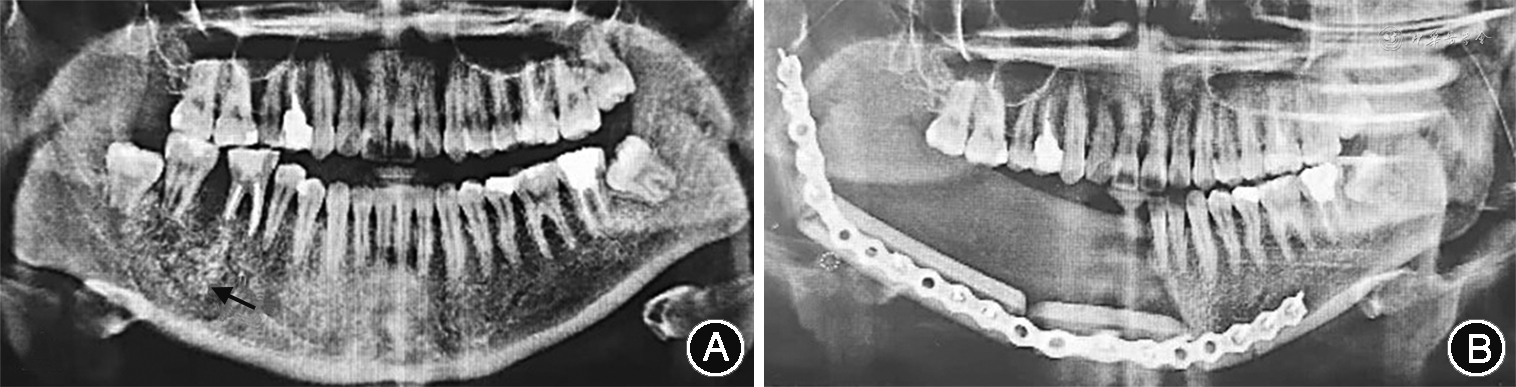

(2)临床及影像学检查:患者双侧颜面部欠对称,右侧下颌区肿胀明显,表面皮肤略发红,皮温略高,无面瘫及局部麻木症状,开口中度受限,开口型基本正常,口内卫生状况可。右侧下颌区自44至磨牙后区牙龈向颊舌侧膨隆明显,触之质韧,似“乒乓球样感”,触痛(+),黏膜表面颜色未见明显异常,44、45、46松动Ⅰ度,47叩痛(+),44—47颊侧前庭沟变浅,余口内黏膜光滑连续,双侧下颌下及颏下未见明显肿大淋巴结。颌骨三维曲面重建CT图像显示,右侧下颌骨区占位性病变,右侧下颌骨骨体部至牙槽骨区见不规则骨性肿块影,密度不均,范围约2.6 cm×4.5 cm×4.0 cm,贯穿牙槽骨,呈膨胀性改变,内见不规则分隔及碎骨片影,病变区域与周围组织分界不清(图1A),邻近颌面部、颌下区脂肪间隙密度增高,双侧颈部及颌下区见多个肿大淋巴结影,余未见异常。

(3)治疗及预后:全身麻醉下手术摘除病灶及节段切除右侧下颌骨骨段,左侧腓骨皮瓣游离移植修复,置入连续钛板(图1B)。患者随诊6个月无复发。